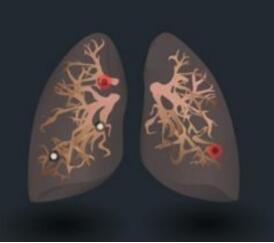

肺內(nèi)結(jié)節(jié),不容忽視,但也不必驚慌。肺部小結(jié)節(jié)并非一定就是肺癌,惡性腫瘤遠(yuǎn)少于良性病變。一般根據(jù)結(jié)節(jié)大小、形態(tài)并結(jié)合你的年齡與吸煙狀況來分析。通常以下情況肺癌的可能性大:年齡在55歲以上;有慢性肺部疾病史和家族史的患者;肺部小結(jié)節(jié)直徑>1厘米;邊緣有毛刺和分葉;內(nèi)部密度不均勻表現(xiàn)為實(shí)性結(jié)節(jié)或者混雜性結(jié)節(jié)。需要注意的是,有吸煙史的人,是肺癌的高危人群,年數(shù)乘以每天吸煙的支數(shù)>400支/年的吸煙患者患肺癌的幾率會(huì)明顯增高。

如果體檢發(fā)現(xiàn)肺部有小結(jié)節(jié),先不要擔(dān)心,它不一定是癌;即使是癌,也不必恐慌,因?yàn)榇蠖嗍菢O其早期的癌癥,只要通過及時(shí)恰當(dāng)?shù)闹委煟峭耆梢匀?。大多?shù)考慮良性病變的肺結(jié)節(jié)只需要定期復(fù)查胸部CT,觀察結(jié)節(jié)變化情況。而高度考慮惡性的結(jié)節(jié)則需要手術(shù)切除。所以在廣大患者發(fā)現(xiàn)肺結(jié)節(jié)時(shí)及時(shí)看醫(yī)生是非常必要的。